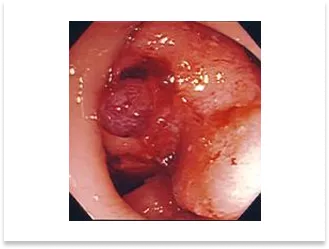

盲腸の小型進行癌症例

術前内視鏡写真